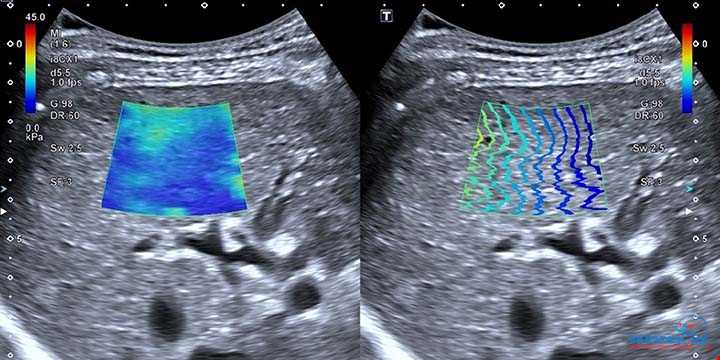

آیا کبد چرب و فیبروز کبدی قابل درمان هستند؟

رادیولوژی اکباتان - مرکز تخصصی فیبرو اسکن و سونوگرافی کبد با تکنولوژی Shear Wave Elastography (Mindray)مقدمهکبد یکی از حیاتی ترین اعضای بدن است که نقش ...

فیبرواسکن کبد در رادیولوژی اکباتان، تشخیص سریع و دقیق بیماری های کبدی

فیبرواسکن چیست؟فیبرواسکن (FibroScan) یک روش غیرتهاجمی و دقیق برای اندازه گیری سختی کبد و تشخیص میزان فیبروز و چربی کبد است. این روش بدون نیاز به جراحی ...